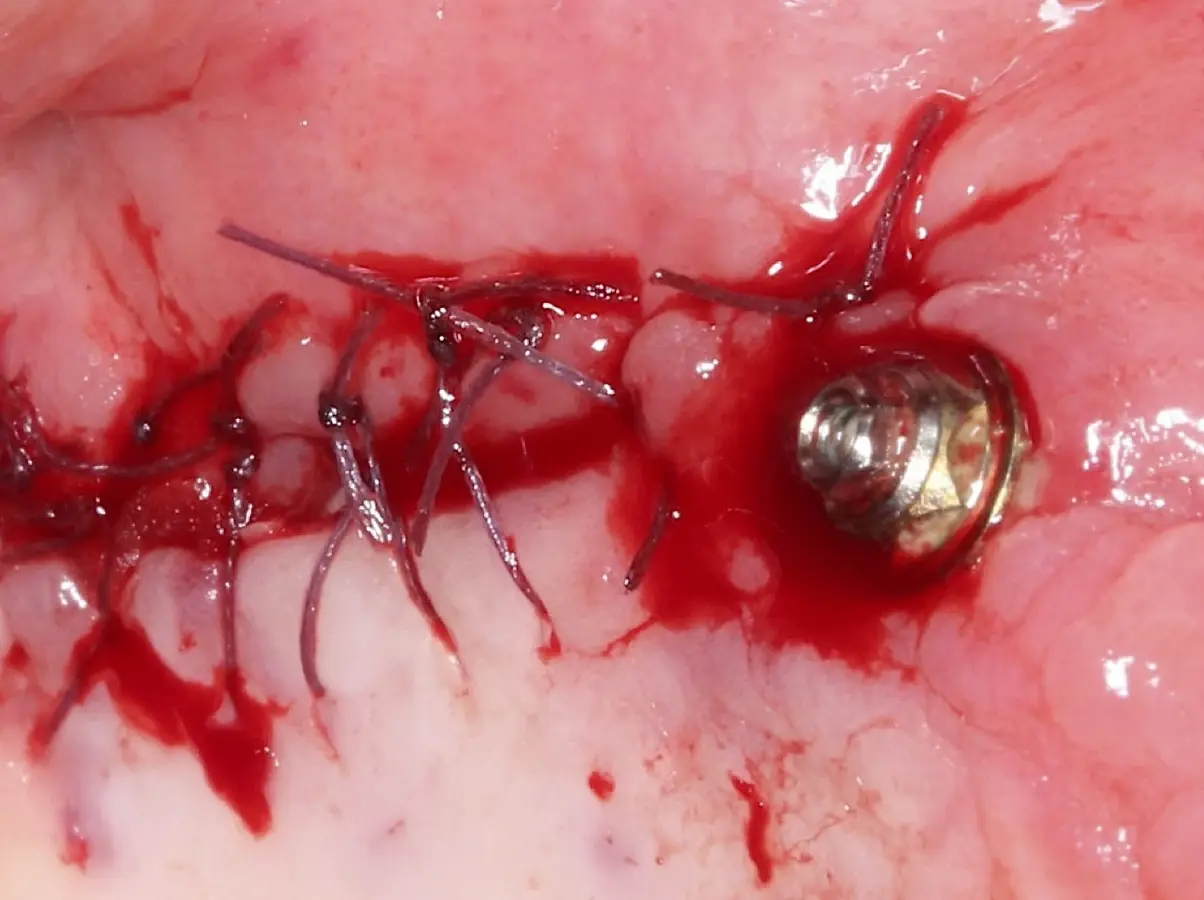

Finalizado el lado izquierdo, continuamos con el levantamiento de piso de seno maxilar del lado derecho.

Figura 22. Afrontamiento de colgajo y sutura.

Figura 23. Delimitación y osteotomía por desgaste de la ventana lateral con el inserto redondo de punta diamantada.

Figura 24. Fractura del bloque óseo con la ayuda de un martillo e instrumento romo.